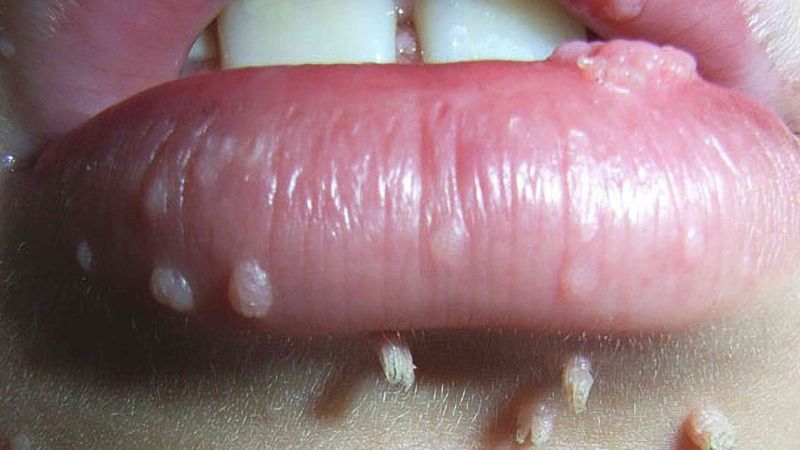

علائم زگیل دهانی، ناشی از ویروس HPV، میتواند شامل زگیلهای قابل مشاهده روی لبها، زبان یا گلو باشد که اغلب به صورت برآمدگیهای کوچک، سفید یا به رنگ گوشت هستند.

HPV باعث ایجاد زائدههای پوستی کوچک، سفید، بژ یا قهوهای رنگی میشود که میتوانند در تمام سطوح بدن، به ویژه در غشاهای مخاطی مرطوب نزدیک دهان، مقعد و اندام تناسلی ظاهر شوند. برآمدگیهای HPV در پشت زبان ممکن است مانند یک ساختار برجسته پر از مایع به نظر برسند. از آنجایی که برآمدگیهای HPV در پشت زبان مسری هستند، میتوانند از فردی به فرد دیگر منتقل شوند. این امر آنها را به یک اتفاق رایج در حفره دهان تبدیل میکند. (منبع)